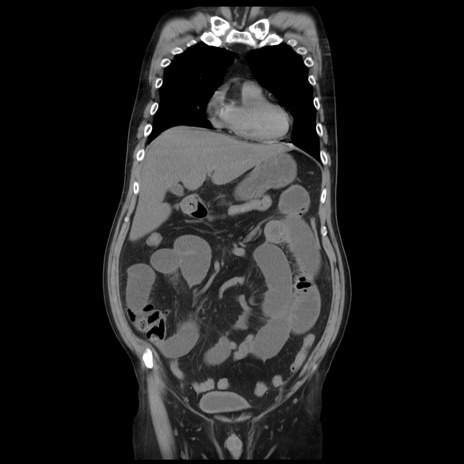

症例20(冠状断像)

【症例】 60歳代男性

【主訴】 腹部膨満、嘔吐

【現病歴】5日前頃より倦怠感を認め食事量減少し4日前の朝嘔吐、食事摂取困難となった。 3日前近医受診し点滴施行され整腸剤などを処方された。 当日他院を受診し、腹部膨満著明、炎症反応の上昇(CRP10.8、WBC11200)あり、紹介受診となる。

【身体所見】 意識JCS1 受け答えがはっきりしないBP 111/57mHg、 P 67bpm、、BT35.2°C、SpO2 97%(RA)、 腹部:膨隆、打診で鼓音あり、全体的に圧痛有り、腸蠕動音(-)、反跳痛ははっきりせず。

【データ】WBC 11400、CRP 14.20

矢状断像